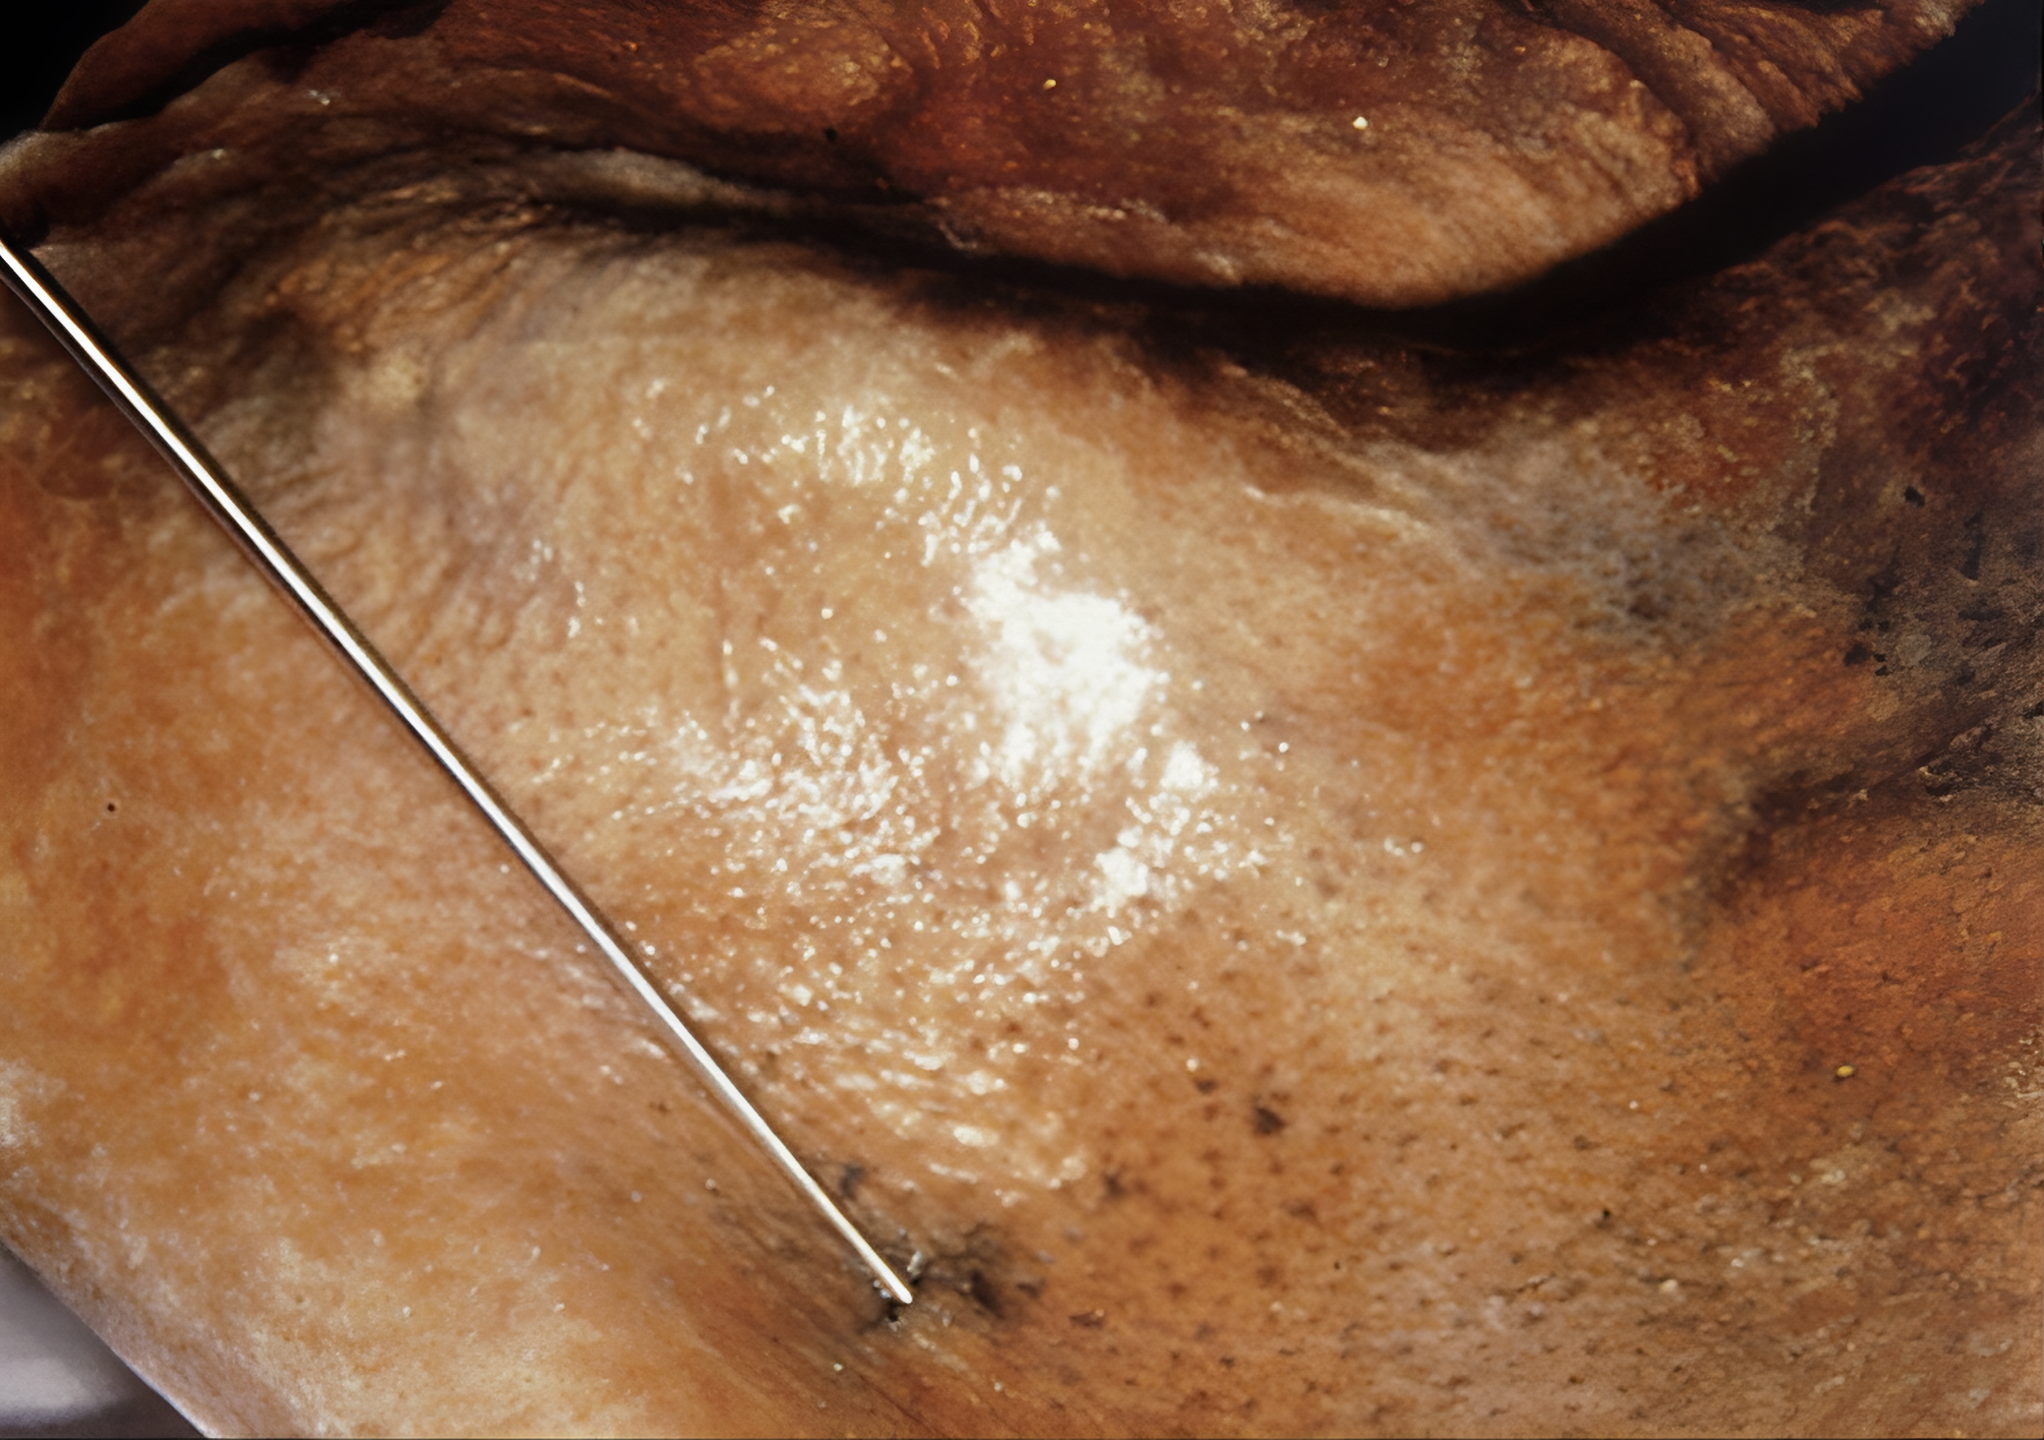

우선 외치에 대한 신체검사가 재개되었는데 이 과정에서 병리학자인 Eduard Egarter Vigl은 외치 어깨 부분 피부에서 매우 수상한 피부 손상을 발견했다.

CT로 찾은 외치 어깨 부분 구멍은 이 피부 손상 부분에서 시작된 것은 분명해 보였다.

이 피부를 뚫고 들어간 무엇인가가 외치 영감님 몸 안으로 파고 들어간 것이다.